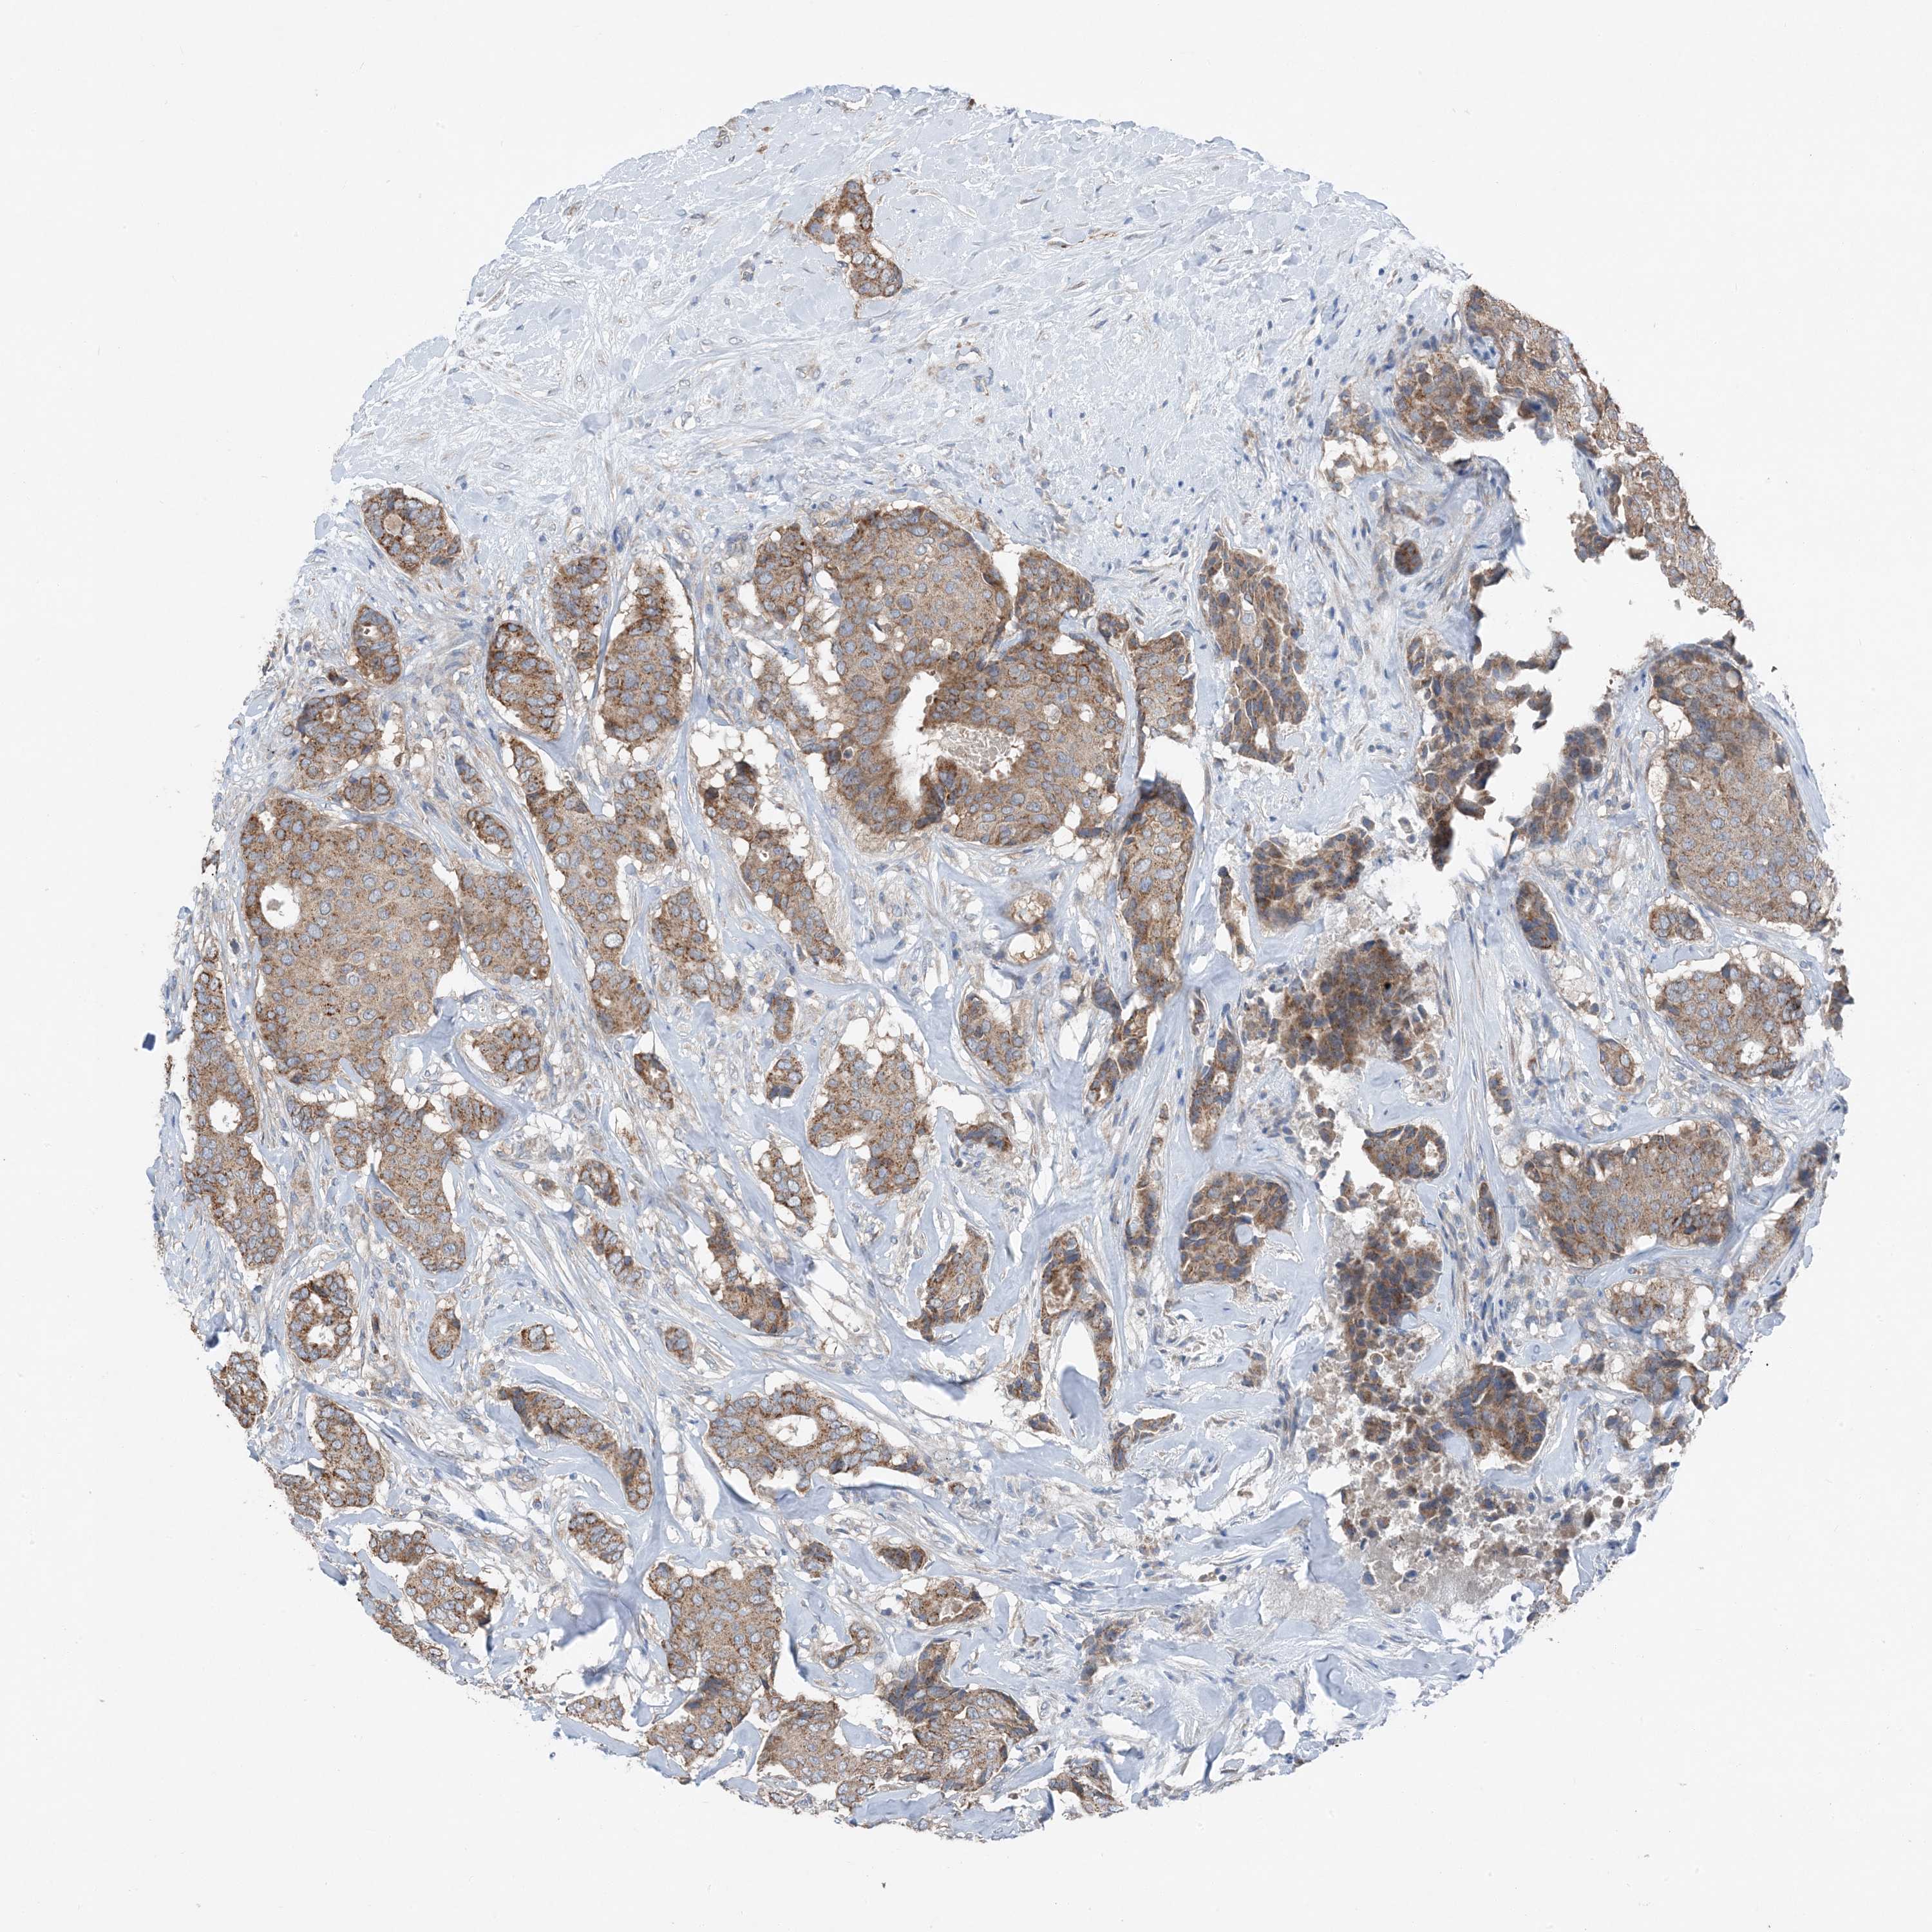

BRCA TCGA BRCA VALIDATION PROTEIN EXPRESSION

ANTIBODIES

AND

VALIDATION